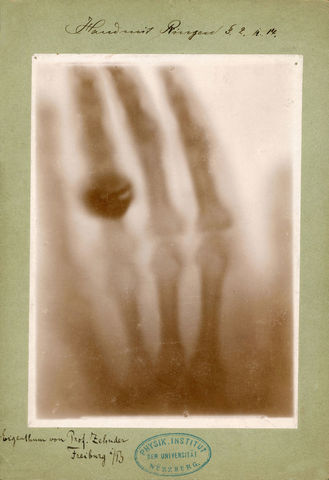

• Primera Radiografía

Primera Radiografía

El profesor Röntgen aplicó los efectos de los rayos X a una placa fotográfica y produjo la primera radiografía de la humanidad. Utilizando la mano de su esposa Bertha Rōntgen